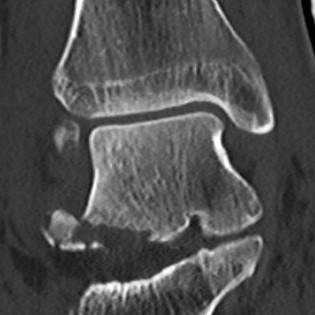

CT

McCrory-Bladin Classification

| Type I |

Type 2A |

Type 2B | Type 3 |

|---|---|---|---|

|

Chip fracture Doesn't involve articular surface |

Larger fracture Involves articular surface talofibular & subtalar join Undisplaced |

Larger fracture Involves articular surface talofibular & subtalar joint Displaced |

Comminuted fracture Involves articular surface talofibular & subtalar |